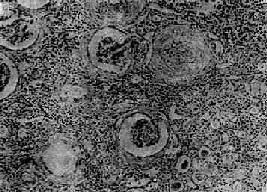

图12-25 慢性肾盂肾炎 有些肾小球毛细血管丛相对正常,肾球囊壁增厚,纤维化,部分肾小管萎缩消失,部分肾小管扩张,腔内有胶样管型;间质纤维组织增生,有大量淋巴细胞等炎细胞浸润 【临床病理联系】 慢性肾盂肾炎常反复急性发作。发作时症状与急性肾盂肾炎相似,尿中有多数白细胞、蛋白质和管型。由于肾小球损害发生较晚,肾小管病变比较严重,发生也较早,故肾小管功能障碍出现较早,也较明显。肾小管浓缩功能降低,可出现多尿和夜尿。电解质如钠、钾等和重碳酸盐丧失过多,可导致缺钠、缺钾和酸中毒。较晚期由于肾组织纤维化和小血管硬化,肾组织缺血,肾素分泌增加,通过肾素-血管紧张素的作用引起高血压。肾乳头萎缩,肾盂肾盏因瘢痕收缩而变形,可通过肾盂造影检见,对临床诊断有一定意义。晚期大量肾组织破坏,可引起氮质血症和尿毒症。 【结局】 慢性肾盂肾炎病程较长,及时治疗,可控制病变发展,肾功能可以得到代偿,不致引起严重后果。若病变广泛并累及双肾者,晚期可引起高血压和肾功能衰竭等严重后果,因此去除诱因和早期彻底治疗非常重要。

图12-24 慢性肾盂肾炎 两侧肾不对称,体积皆缩小,表面颗粒状,有不规则的瘢痕 镜下见病变呈不规则片状,夹杂于相对正常的肾组织之间。瘢痕区的肾组织破坏,肾间质和肾盂粘膜纤维组织大量增生,其中有大量淋巴细胞、浆细胞、单核细胞和多少不等的中性粒细胞浸润。其间的小血管常有炎症,管壁增厚,管腔狭小。肾小管多萎缩、坏死由纤维组织替代。有些肾小管腔扩张,腔内有均匀红染的胶样管型,形似甲状腺滤泡。有些肾小管腔内还有多数中性粒细胞。肾小球多萎缩、纤维化或玻璃样变(图12-25)。病灶周围的肾组织内肾小球尚完好,有些肾小球的球囊壁增厚,纤维化。有些肾单位呈代偿性肥大。